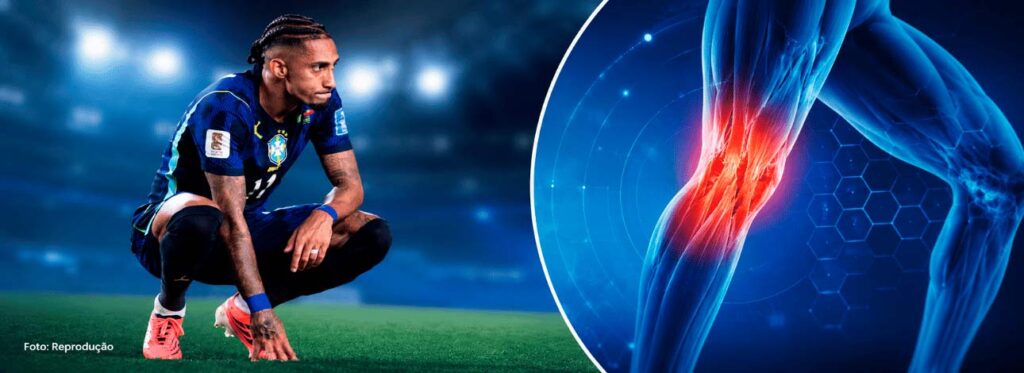

Casos como da lesão de Raphinha, atacante da Seleção Brasileira, levantam questionamentos sobre o por quê do retorno de uma lesão já tratada

ratura de jogador do Canadá chama atenção para a gravidade das lesões ósseas. Entenda como o ortopedista atua, exames e recuperação!

Entenda a importância do exame de Ressonância para diagnóstico de lesões e como ele traz mais precisão com imagens detalhadas